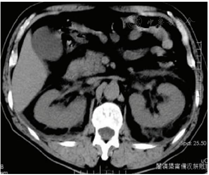

辅助检查:血常规:WBC 25.7×109/L,NE 60.2%,PLT 49×109/L。肝肾功能:ALT 360 U/L,AST 175 U/L,CREA 207 μmol/L。凝血:PT 16.7 s,APTT 74.7 s。心电图:窦性心动过速。完善胸部CT检查:未见明显异常(图1)。腹部CT:肾脏形态不规则,体积局部增大,周围渗出边缘毛糙(图2)。